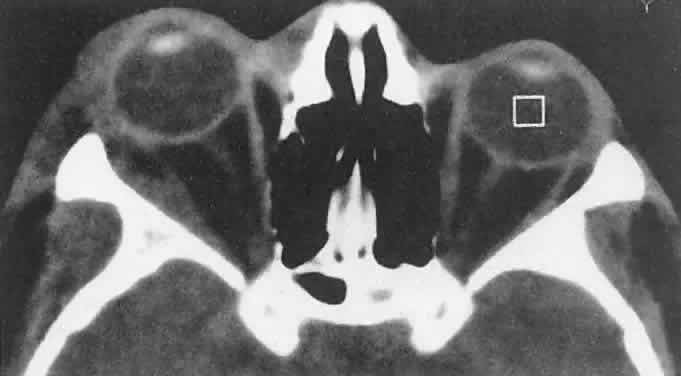

tissue).40,41 Involvement of the facial bones and orbit is less common in the North

American cases, but invasion of the orbit from the sinuses may occur42,43 (Fig. 4).  Fig. 4. Burkitt's lymphoma involving the posterior ethmoids, skull base, and

both orbital apices in a 5-year-old boy. Fig. 4. Burkitt's lymphoma involving the posterior ethmoids, skull base, and

both orbital apices in a 5-year-old boy.

|